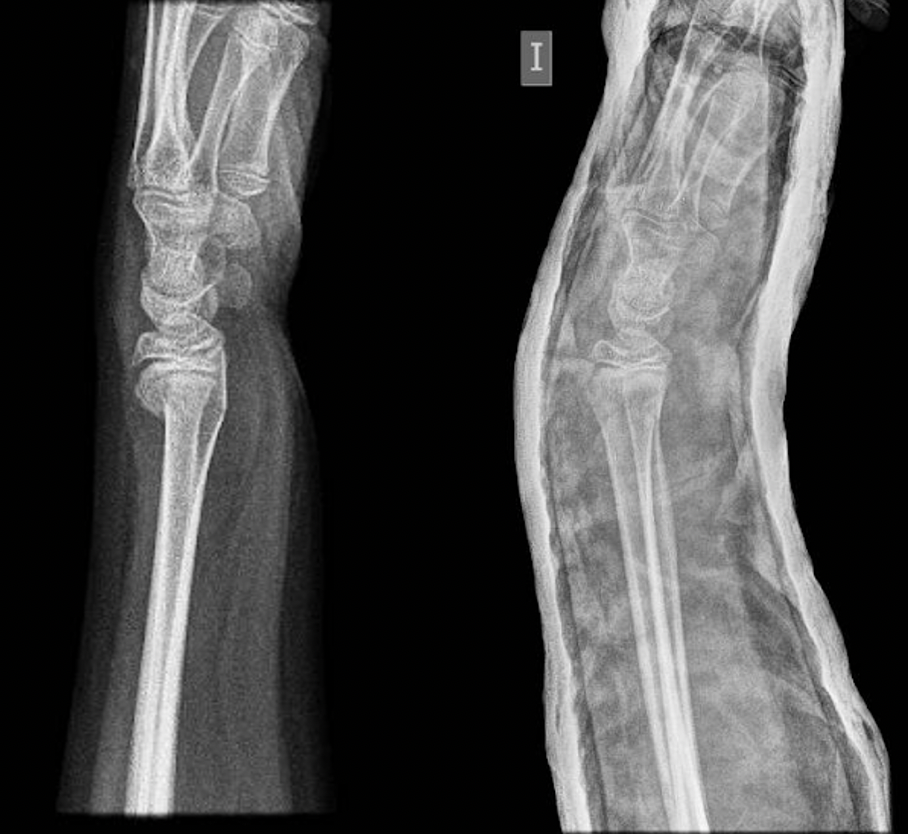

Fractura de radi en un pacient pediàtric. La fractura presentava un desplaçament que va requerir reducció i col·locació de guix per mantenir la reducció fins a la curació.